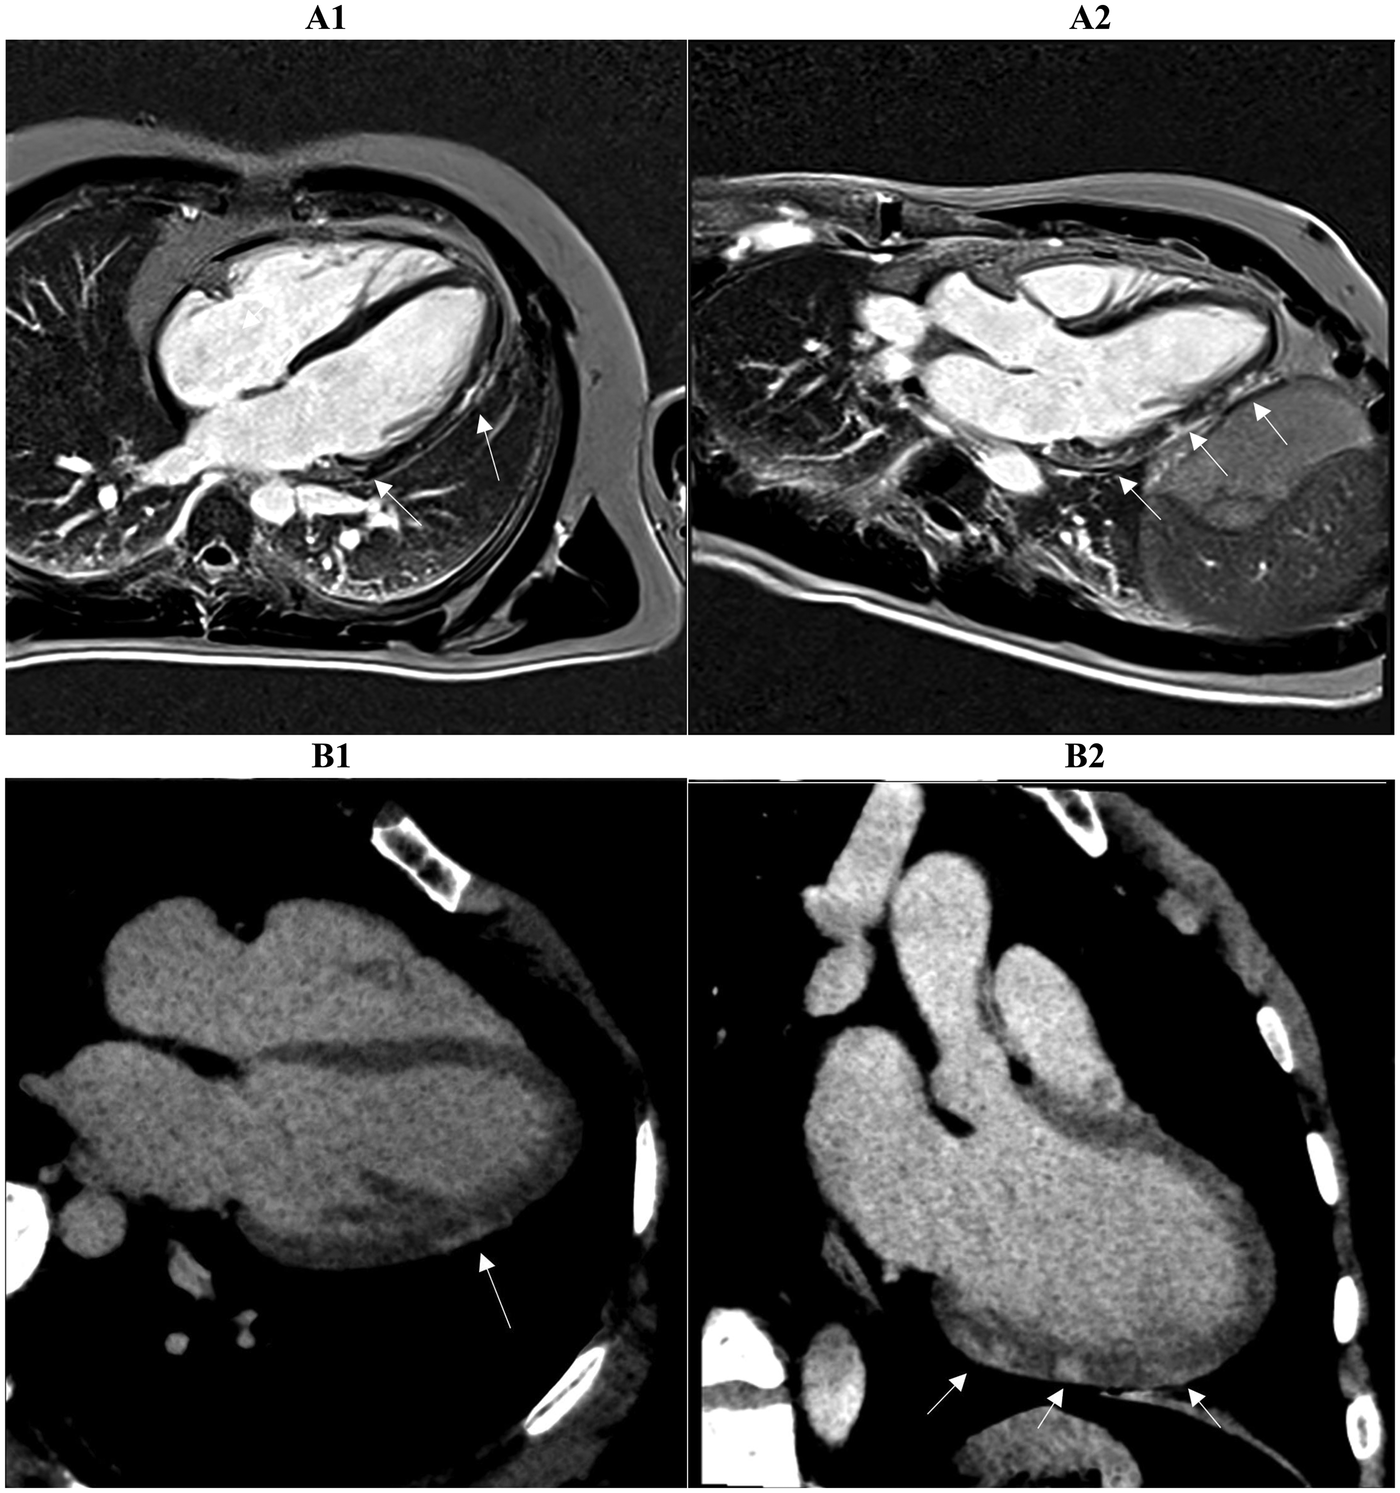

Figure 3

Two myocardial tissue characterization slices on CMR (A1, A2) and CCTA (B1, B2) in the same patient diagnosed with myocarditis at discharge are shown. Both the long-axis four-chamber and three-chamber views reveal intramural or sub-epicardial enhancement (arrows) with 80% segmental concordance between the imaging techniques, based on matching presence or absence of enhancement in corresponding myocardial regions. CMR, cardiac magnetic resonance; CCTA, coronary computed tomography angiography.

On a segment-by-segment comparison (Figure 3), LIE and LGE findings agreed in 17 of 21 patients (81 percent). Complete segmental concordance was present in all 8 MINOCA cases (Figure 4) and in 2 myocarditis cases. In the remaining myocarditis patients, concordance ranged from 25 to 83 percent of affected segments (Figure 5). Overall agreement (Table 3) was 100 percent in MINOCA and 15 percent in myocarditis (P < 0.001). Subendocardial enhancement correlated strongly with a final diagnosis of MINOCA (Spearman's ρ = 0.82, P < 0.001).